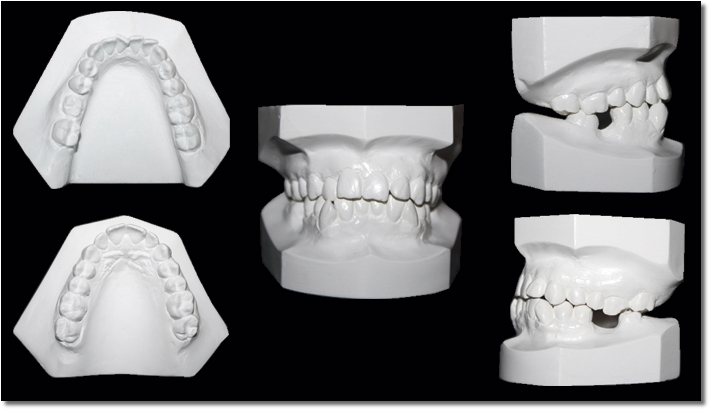

Servicios adicionales

Fotografías Clínicas Extraorales

Fotografías Cimica Intraorales

Modelos de Vitrina

Modelos de estudio

Modelos de trabajo